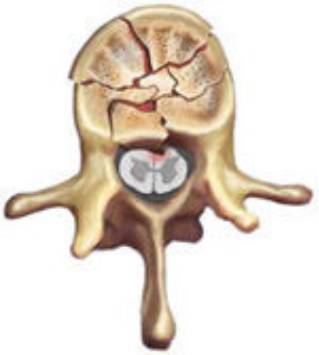

burst骨折

椎体轴向压力造成的骨折,通常发生骨折碎片向四周移位,有时候可以突入椎管。可以发生在颈椎、胸椎或腰椎。